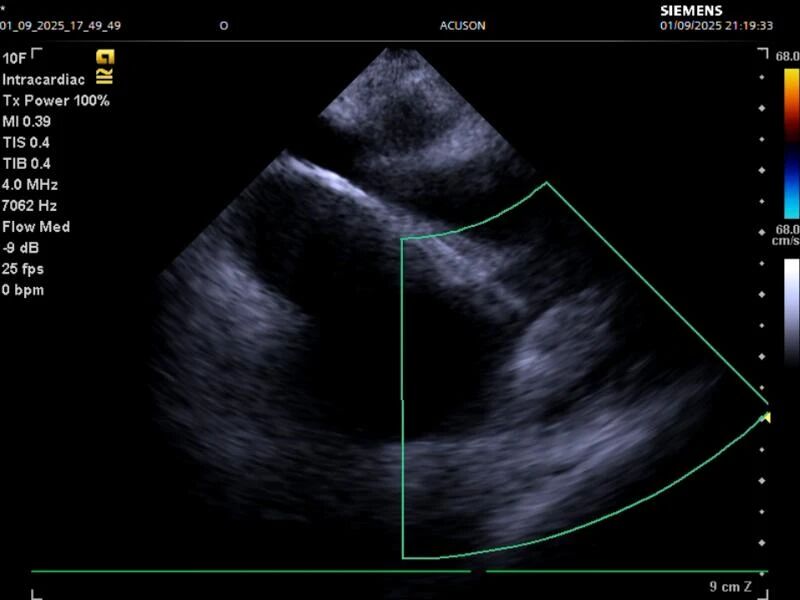

本次手术的亮点在于ICE(心腔内超声)的精准实时引导,相比传统方式具有视野清晰、定位准确、患者不适感轻等优势,能大幅提高手术安全性与有效性,同时减少辐射暴露,真正实现了微创、精准、安全、高效。